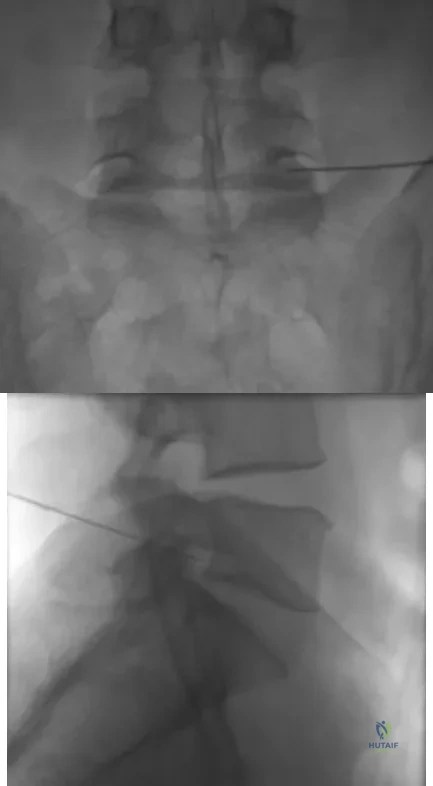

Figures 61a and 61b show the CT and MRI scans of a 40-year-old man who has hip pain. He undergoes total hip arthroplasty and curettage and cementation of the lesion as shown in Figure 61c. Histopathologic photomicrographs of the curettage specimen are shown in Figures 61d and 61e. What is the best course of treatment?

A 13-year-old boy has had a painless mass in the arm for the past 2 months. An MRI scan and biopsy specimens are shown in Figures 46a through 46c. What is the most likely diagnosis?